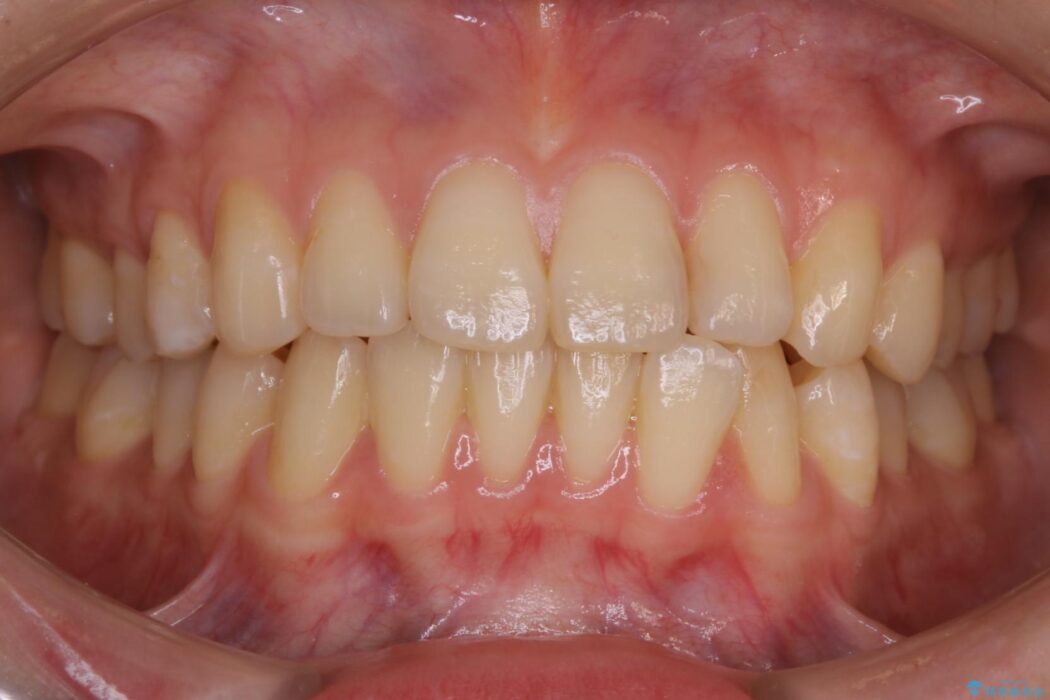

下の前歯のガタつきが気になるとご来院された患者様です。

インビザラインのライトパッケージにて、歯列拡大とディスキング(IPR)をを行いスペースをつくり非抜歯で治療を行いました。